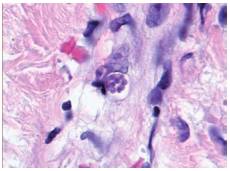

Histopathology of skin lesions was positive and immunohistochemistry for toxoplasmosis confirmed the presence of the parasite (figure 2 and figure 3). Molecular studies with blood and cerebrospinal fluid (CSF) PCR were also positive forToxoplasma(7). Central nervous system magnetic resonance (MR) did not show focal lesions.

To our knowledge, this is the first heart transplant patient reported in the literature presenting toxoplasmosis with cutaneous manifestations. Such cutaneous involvement is quite rare, and only a few cases have been reported in immunocompromised patients with great variability in the appearance of skin lesions. Generalized rash, erythema multiform-like lesions, nodular lesions and vesicular varicella-like lesions have been described (19-21). Skin biopsies confirmed the presence of the parasite, but histopathological findings are variable. The involvement of the colon is also unique in this patient.